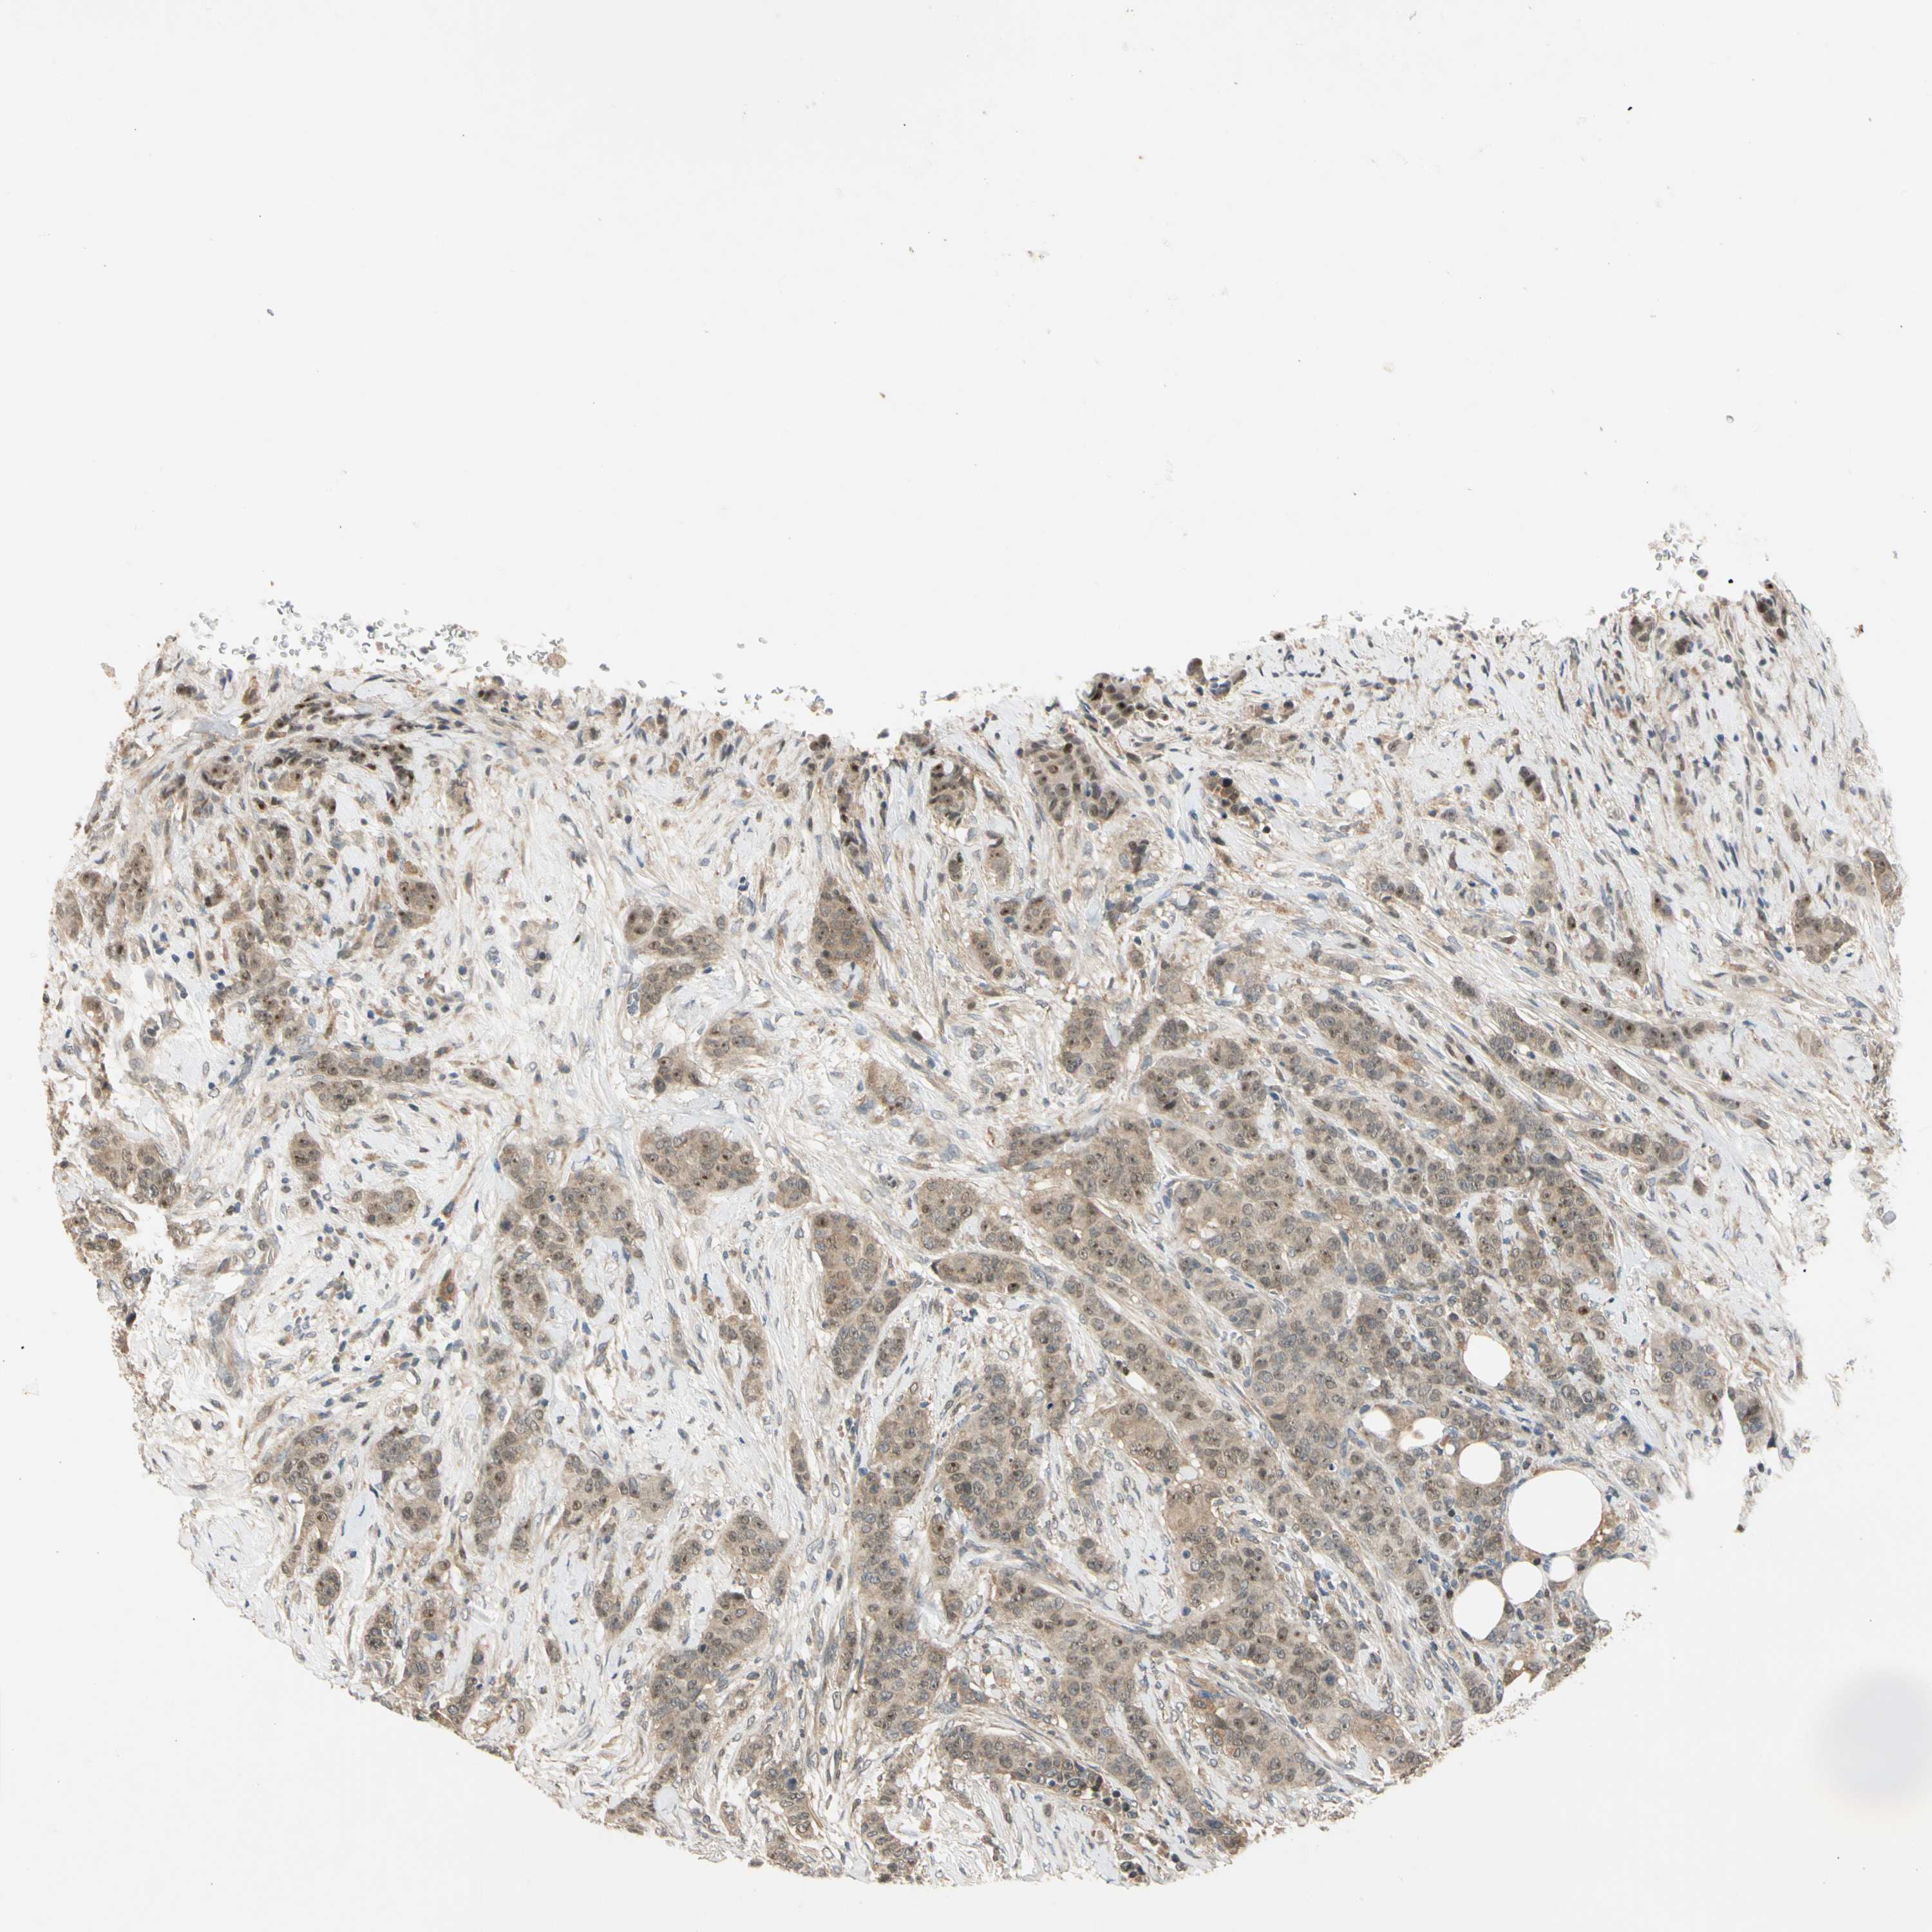

CANCER BREAST CANCER Show tissue menu

BRCA TCGA BRCA VALIDATION PROTEIN EXPRESSION